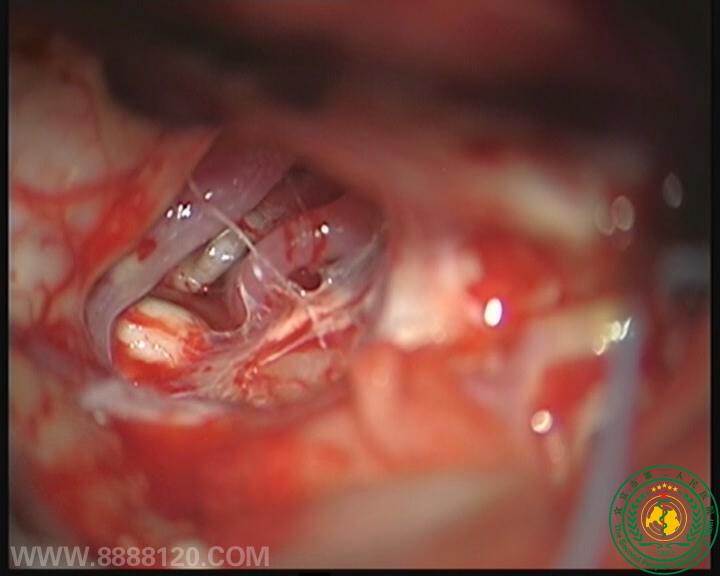

我科顺利完成颅内毗邻脑干肿瘤切除术一例

我科顺利完成颅内毗邻脑干肿瘤切除术一例5907